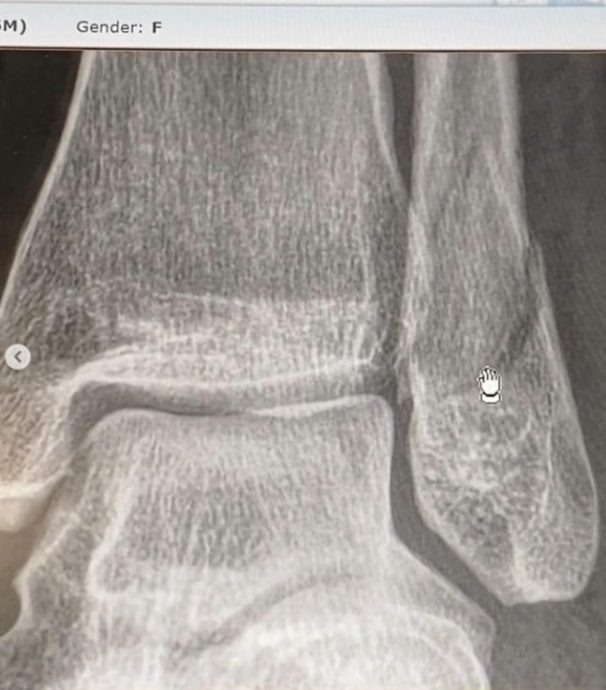

林佩琦摔伤左脚骨折 植入8钢钉留4公分疤

(吉隆坡26日讯)Emily林佩琦4天前发文透露自己意外摔伤,导致左脚骨折,她今早动了2小时手术,在左脚植入8枚钢钉,目前得休养6星期,所有工作暂时全面停摆。问老公袁锦伦是否全程陪伴?她表示,“必须的。”还爆说老公取笑她平日骑马、攀岩都没事,没想到首次进院动手术,竟是因为大意失足。

她表示,左脚会留有4cm(公分)的疤,“这是我人生中第一次进手术室,麻醉师很贴心,把针头安排在手肘内,担心放在手背会留疤。”虽然这次跌倒很不幸,但她非常感谢遇上的每位贵人,“剧组人员上下包括马来演员们都很照顾我,连他们的助理都很帮忙。”她也因为被迫辞演一部电影和剧集而打趣表示,“这次摔倒真的很贵。”